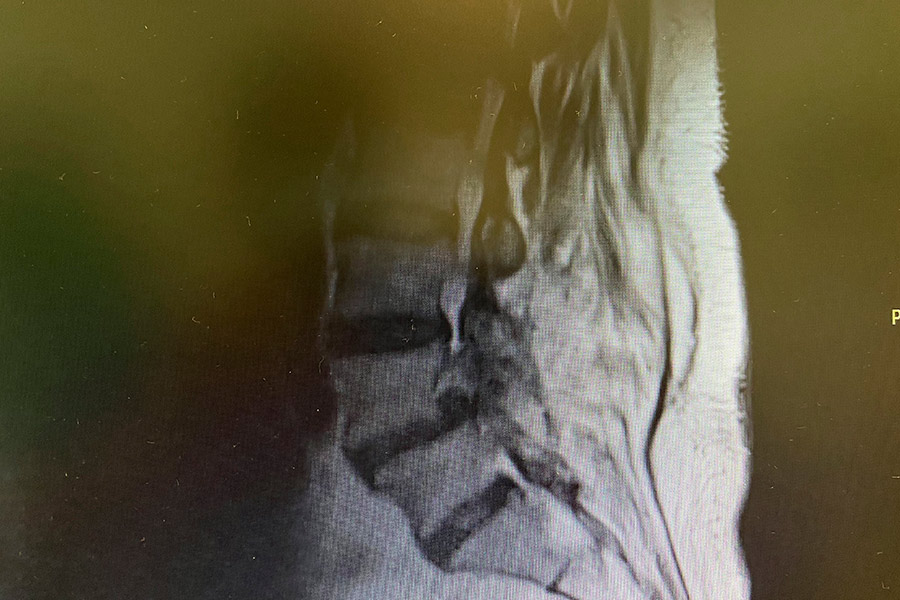

Hernia-discal-foramidal-josefa-carro-post

Tras finalizar la operación, de unos 45 min de duración, el Doctor Elgeadi consigue liberar el foramen en la zona donde se encontraba la hernia, por lo que la raíz nerviosa ya no se encuentra comprimida.

Dada la anterior operación, la paciente tenía varias cicatrices que se han tenido que esquivar, dificultando la operación. Se ha aplicado también un tratamiento de láser, eliminando así la sensibilidad dolorosa que sufría en las articulaciones posteriores.